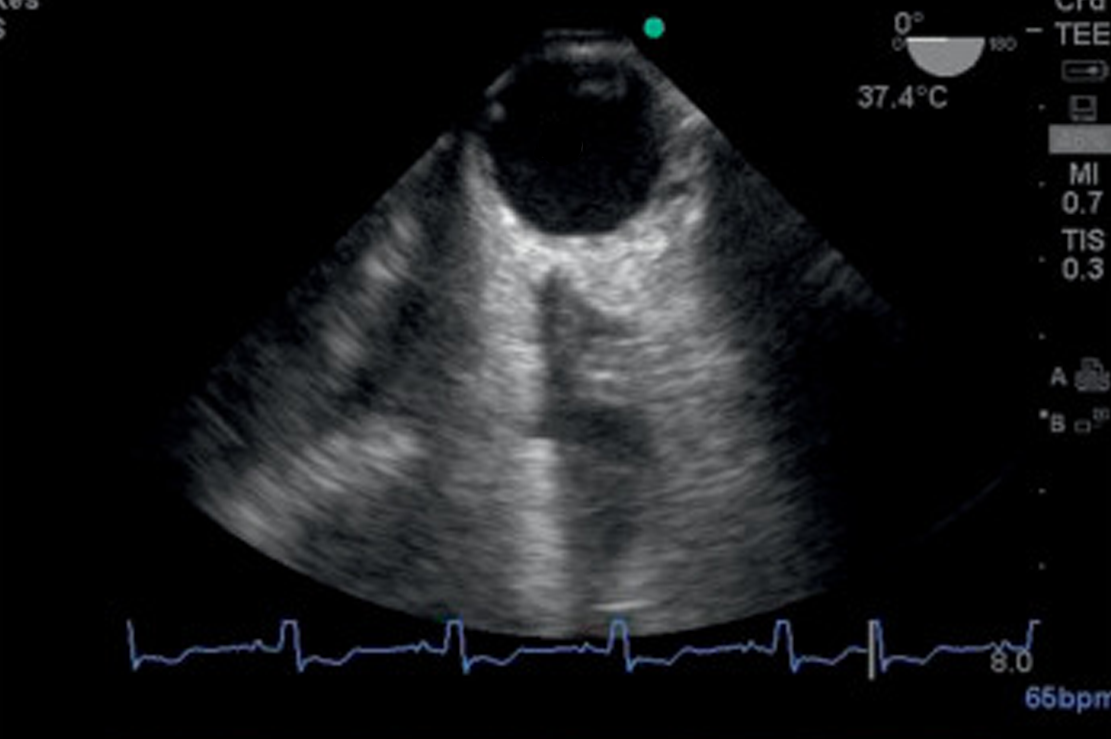

We have added 2 exciting workshops but space is limited. One workshop will be Feb 12th at noon-15:00 and the other Feb 13th. 09:00-12:00 Critical Care Transesophageal Echo: TEE for the general intensivist

Once regarded as a tool only for the CV ICU, the reliability, image clarity and ease of imaging of TEE is now being put to use increasingly in the general ICU. As critical care echo becomes the dominant means through which intensivists diagnose and manage shock states, TEE offers many advantages over TTE and is an evolving tool in the intensivist’s tool kit. In this unique hands-on workshop, using high-fidelity simulators, image interpretation sessions using actual cases and lectures from leaders in this nascent field, participants will be able to participate in the cognitive and procedural aspects of critical care TEE for the generally ICU patient.